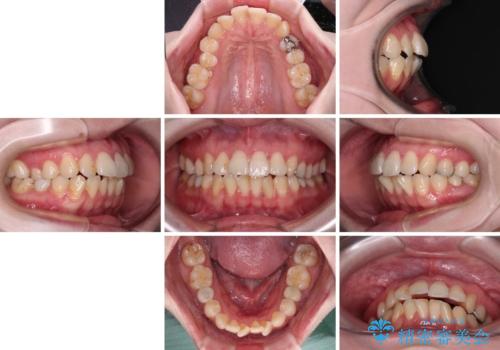

開咬と前方に飛び出した前歯 インビザラインによる矯正治療

- 上下前歯の非接触と叢生を気にして来院された患者様です。

開咬の改善はインビザラインの最も得意とするところであるため、インビザラインを用いて矯正治療を行うこととしました。

舌の突出癖改善のトレーニングをしっかりと行っていただき、上下前歯が接触する咬み合わせを達成することができました。